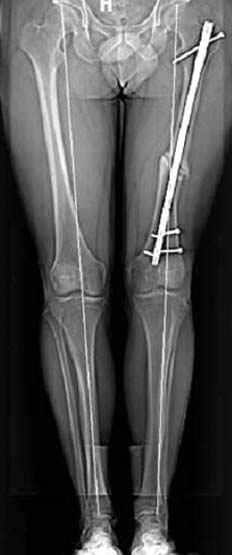

Несколько снимков из моей коллекции, чтобы разьяснить, почему мы до сих пор делаем различные варианты остеотомии.

N3 рисунок окончательный снимок, после операции моя рентгенограмма должен выглядеть примерно как эта картина. На N4 снимке клин перед удалением; N5 послеоперации 3 нед.; N6 окончательная рентгенограмма.

Интересно бы посмотреть рентгенограмму таза (оба сустава) а также рентгенгорамму с захватом коленных суставов (по Dror Paley).

пластическая модель; и коррекция бедра аппаратом Илизарова.